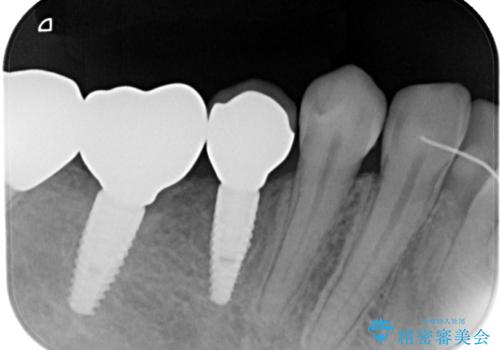

割れてしまった奥歯 インプラント治療

土台の材料を外して顕微鏡下で確認したところ、歯根にまで及ぶ破折が認められたため、インプラント治療を行うこととしました。

他にも銀歯や欠損となっている歯に対しての治療も希望されたため、補綴治療を行うこととしました。

インプラント治療をきっかけに、銀歯を全てセラミックに替えていきました。